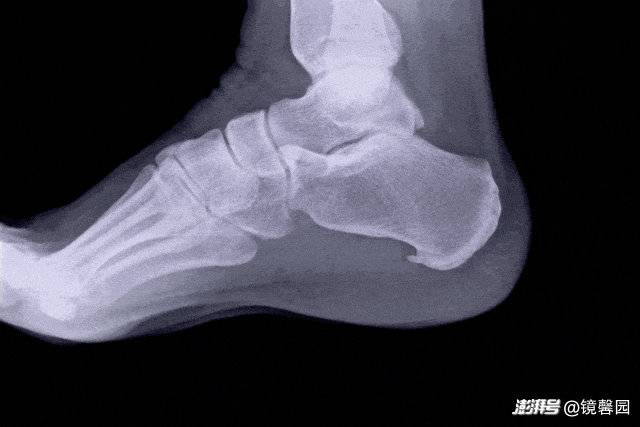

去医院找骨科一看,一拍就发现脚后跟居然长了“骨刺”!

脚底x片有骨刺(刺激外展神经引起疼痛);